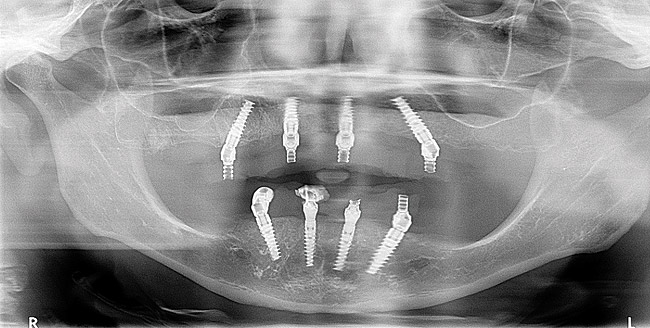

A radiograph was taken to verify that the provisional with temporary sleeves was adapted perfectly to the shoulder of the multi-unit abutment as this prosthesis was used as the verification jig (Figure 7). The composite implant plug was removed to gain access to the multi-unit abutment screws that were then removed. Twenty-millimeter guide pins were inserted through the provisional. The patient could not close her mouth at this point.

Figure 7  A postoperative panoramic radiograph showing implant placement.

Figure 7